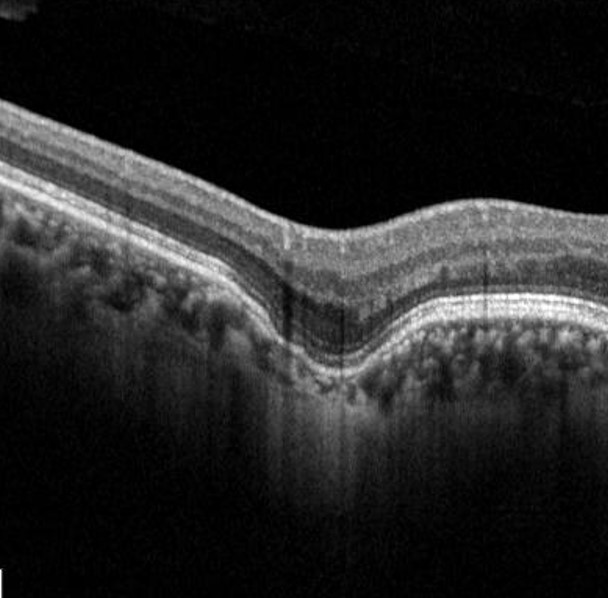

OCT is most useful for the diagnosis of FCE, showing a focal concavity of the choroid with underlying dilated choroidal vessels.

In a conforming FCE, the outer retina conforms to the choroidal excavation with the attachment between the photoreceptors tip and RPE is preserved (two case examples follow). In a non-conforming FCE, the photoreceptor tips and RPE are separated to form a subretinal space.

Case 1 (Conforming)

A 44-year-old Asian female with best-corrected visual acuity of 6/7.5+2 (20/25+2) in the right eye.